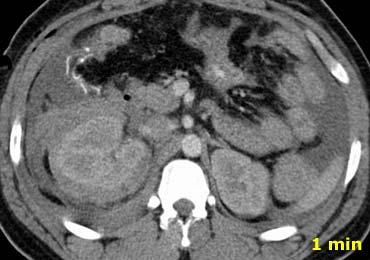

-

Trong pha mạch máu ở phút thứ 1, có hiện tượng thoát thuốc cản quang và dịch trong các rãnh cạnh đại tràng, cho thấy vi phạm phúc mạc.

Ngoài ra còn có khối máu tụ trong khoang quanh thận. - Trong pha muộn, có thêm hiện tượng thoát thuốc cản quang, mặc dù chưa rõ liệu đó là do chảy máu tích cực hay thuốc cản quang thoát ra từ hệ thống thu thập nước tiểu

- Trong pha bài tiết, rõ ràng có sự vi phạm hệ thống thu thập nước tiểu